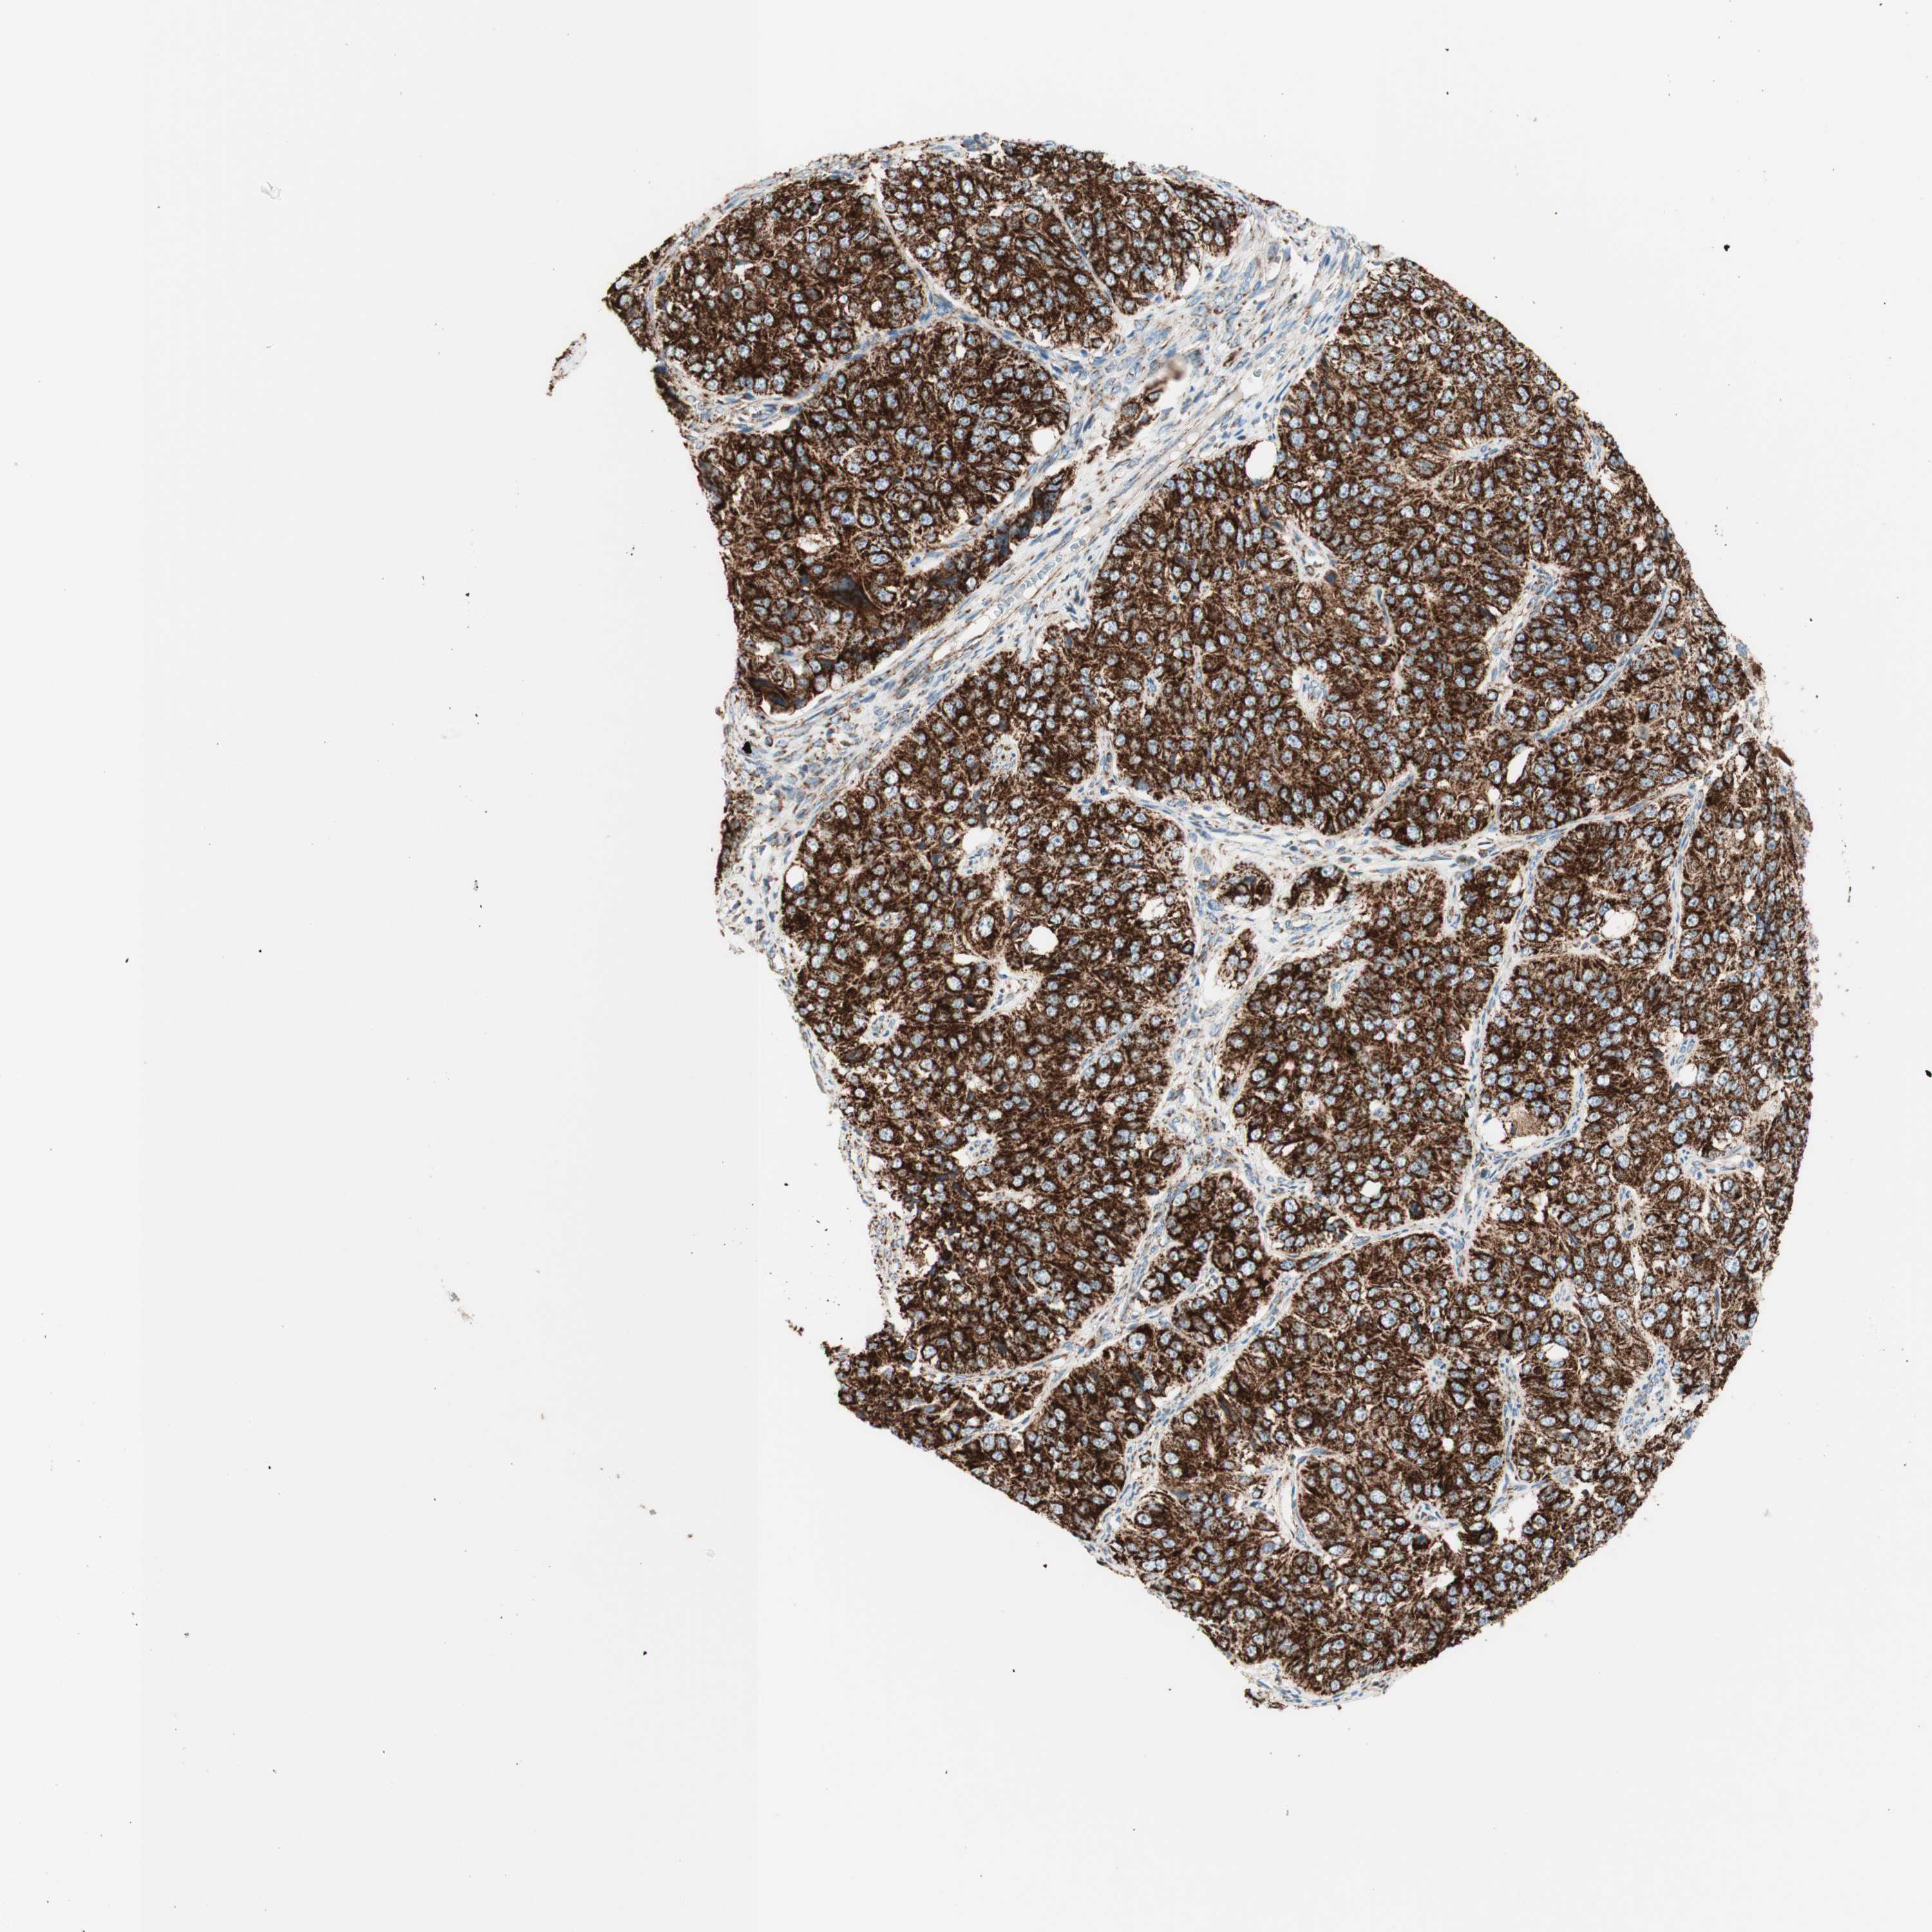

OVARIAN CANCER - Protein expressioni

A mouse-over function shows sample information and annotation data. Click on an image to view it in a full screen mode. Samples can be filtered based on level of antibody staining by selecting one or several of the following categories: high, medium, low and not detected. The assay and annotation is described here.

Note that samples used for immunohistochemistry by the Human Protein Atlas do not correspond to samples in the TCGA dataset.

Antibody stainingi

Antibody staining in the annotated cell types in the current human tissue is reported as not detected, low, medium, or high, based on conventional immunohistochemistry profiling in selected tissues. This score is based on the combination of the staining intensity and fraction of stained cells.

Each image is clickable and will lead to virtual microscopy that enables deeper exploration of all samples and also displays staining intensity scores, fraction scores and subcellular localization as well as patient and tissue information for each sample.

Antibody CAB005585

Cystadenocarcinoma, serous, NOS

Carcinoma, endometroid

Cystadenocarcinoma, mucinous, NOS

Carcinoma, NOS